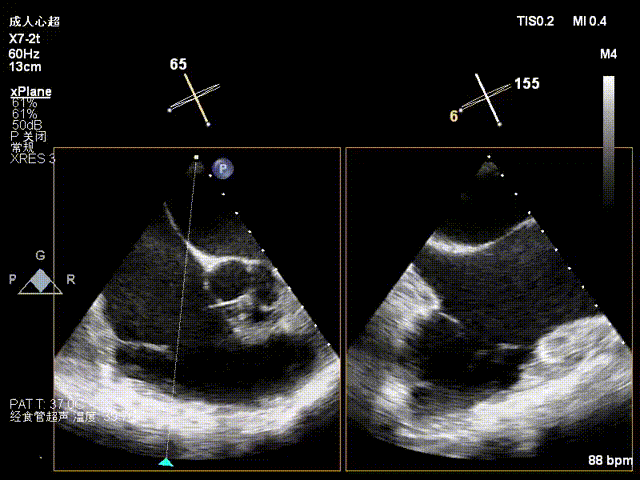

1. The first 14T device was positioned under the mid-esophageal bicaval view on TEE, and the tip of the delivery catheter was observed to point to the posterior-septal commissure of the tricuspid valve using 3D mode.

2. Under 3D mode switched to MPR-MultiVue mode, the trajectory was adjusted to anchor the tricuspid annulus.

3. The pull test was completed under MultiVue mode.

4. After opening the clipping component, the orientation was adjusted under 3D mode.

5. Apposition to the tricuspid annulus under 3D mode.

6. Under the guidance of MultiVue mode and DSA, the anchoring pull rod was retracted and the clipping component was closed to complete the clip application.

7. Coronary artery course and blood supply were evaluated under DSA (the course of the coronary artery was altered, but blood supply remained normal).

The first clip was initially implanted at the posterior‑septal commissure, which resulted in deformation of the coronary artery course. The first clip was released and repositioned toward the septal leaflet, with the clip arms opened to cross the posterior‑septal commissure before re‑implantation.

Initial DSA after clipping indicated compromised blood supply. The clip was therefore released, repositioned, and redeployed.

The second clip was deployed toward the septal leaflet, crossing the posterior‑septal commissure and positioned flush with the tricuspid annulus.

8. A second 14T device was selected and deployed following the same procedure.

During implantation of the second clip, anchoring was performed at the annulus near the leaflet base. Intraoperative DSA showed no impact on the coronary arteries, and good right coronary perfusion was confirmed after deployment.